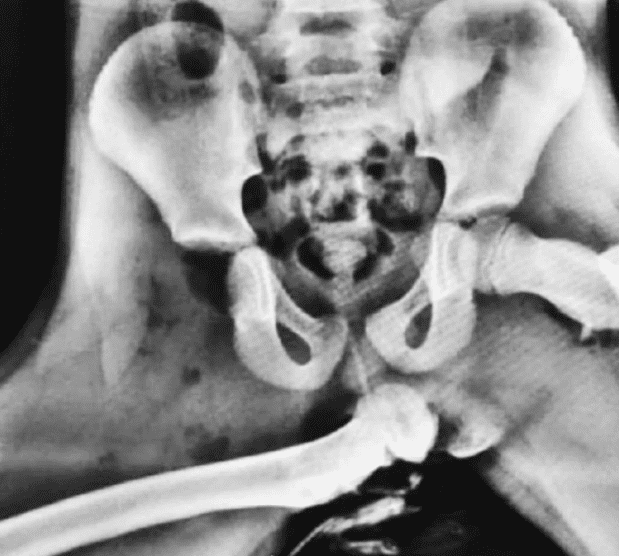

腳放儀表盤上的后果:股骨從下體刺穿,看樣子是女生?

來自一場車禍后的股骨,股骨從下體刺穿,據(jù)說當時坐副駕駛的人,腳翹翹的放在儀表盤上方的位置,還好不是男生,在汽車駕駛中,將腳放在儀表盤上可能導致發(fā)生嚴重的后果。

女生股骨從下體刺穿(圖)

如果車輛發(fā)生碰撞或緊急制動,空氣袋會迅速充氣,并對乘客進行保護,但是如果此時乘客的腳放在儀表盤上,可能導致腳部受到嚴重的損傷甚至斷裂。因此,強烈建議不要將腳放在儀表盤上,以確保安全駕駛。...